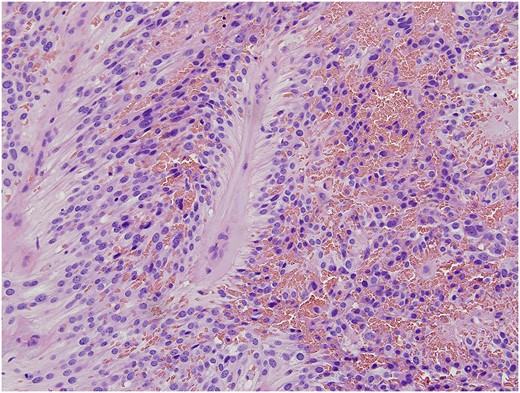

Final pathology revealed a moderately cellular neoplasm with cellular processes extending around blood vessels, formation of perivascular pseudorosettes, and areas of myxoid degeneration (Fig. 1). The neoplastic cells were strongly positive for glial fibrillary acidic protein (GFAP), CD-99, and CD-56, all of which supported the morphologic diagnosis of ependymoma (Fig. 2). The cephalad margin was positive for tumor. A follow up magnetic resonance (MR) of the pelvis and neuraxis was obtained, which demonstrated post-surgical changes and no evidence of persistent tumor (Fig. 3). After evaluation by neurosurgery, full neuro-axial imaging was performed and did not show any evidence of tumor or additional pathology. Excision of the positive cephalad margin and adjuvant chemotherapy or radiotherapy was not recommended. Long-term surveillance with frequent clinical examinations and pelvic MR was established.

Classic morphologic features of ependymoma including moderately cellular neoplasm composed of cells with mildly pleomorphic round and oval nuclei in a fibrillary background. The neoplastic cells arranged as solid sheets and cords of cells with occasional cribriform pattern. The eosinophilic cellular processes extended around blood vessels with formation of perivascular pseudorosettes. Areas of myxoid degeneration, necrosis and hemosiderin deposition was evident.